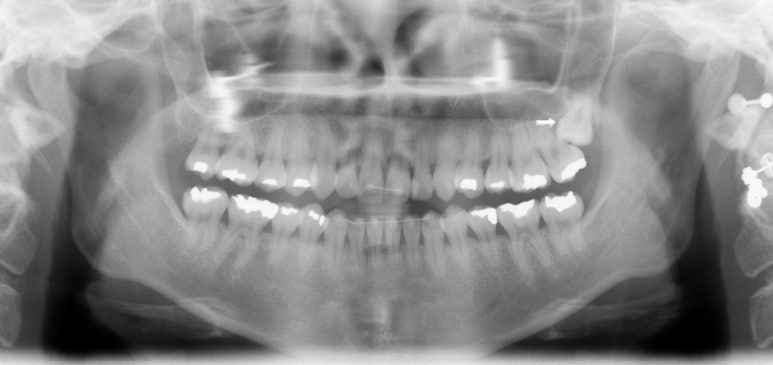

치아 교정 치료는 기능성과 심미성이 적절한 조화가 이루어져야만 성공적인 치아 교정이라 할 수 있습니다.그렇기에 실력있는 의료진이 축적된 노하우와 기술로 부작용을 최소화하여 환자가 원하는 이상적인 치료 결과를 만들어 내야 합니다. 개인마다 식습관, 치아의 배열, 얼굴의 형태, 라이프스타일 등 전부 다 각기 다르므로 이 모든 항목들을 꼼꼼하게 체크한 후 개개인에게 맞는 맞춤 진단이 필요합니다.

클리피씨 교정, 2D 교정, 콤비 교정, 설측 교정, 부분 교정등의 다양한 교정 치료